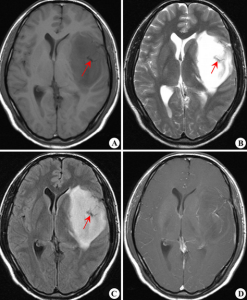

腦部膠質瘤為膠質瘤中最常見的一種,約占40%左右。病理分型為Ⅰ級(星形細胞瘤),Ⅱ級(星形母細胞瘤),Ⅲ~Ⅳ級(多形膠母細胞瘤)。Ⅰ~Ⅱ級星形細胞瘤為低度惡性,起病緩慢,腫瘤在CT及MR的表現多為實性或囊性,邊界不清,腫瘤實性部分或囊性結節均可強化。臨床表現與病灶部位不同進行性地出現相應的症狀,並最後出現顱高壓的症狀。Ⅲ~Ⅳ級的多形膠母細胞瘤起病快速,為惡性度最高的腫瘤,多生長於大腦半球,因腫瘤生長迅速,腫瘤中心可有多處壞死及出血,CT及MR均明顯強化。周圍可伴大片腦組織的水腫。